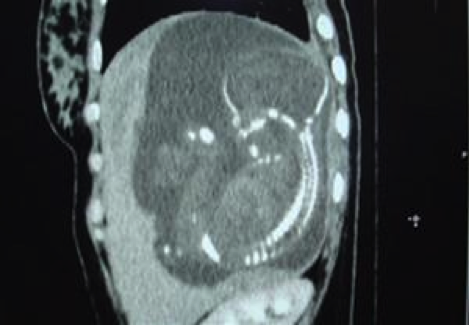

Tại Bệnh viện Từ Dũ, siêu âm và chụp CT tại Trung tâm Medic, phát hiện một thai sống khoảng 22 tuần trong ổ bụng vùng dưới hoành phải (dưới gan phải). Kích thước khối thai là 12x15x17cm. Bánh nhau dày 47mm, xâm lấn gan phải và có mạch máu nuôi xuất phát từ động mạch gan phải. Chẩn đoán: thai dưới gan, chỉ định mổ lấy khối thai và tiên lượng cuộc mổ khó nên mời phẫu thuật viên Bệnh viện Chợ Rẫy kết hợp cùng mổ.

Hình 5. Thai nằm dưới gan (ngôi ngược) |

Hình 6. Thai trong ổ bụng. Thai ngôi ngược, có hình ảnh giống như thai trong tử cung nhưng không rõ hình tử cung, khối thai nằm dưới gan nên thấy đầu các xương sườn (Nguồn: ảnh phim Medic) |